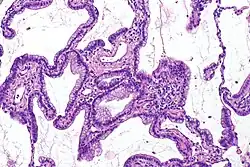

- Histopatología

- Está constituido por células binucleadas que tienen mucina en el 80% de los casos. Las células por tanto producen moco, forman una sola hilera de células prismáticas con proliferación papilar, tubular o acinos y algunas veces glándulas completas.